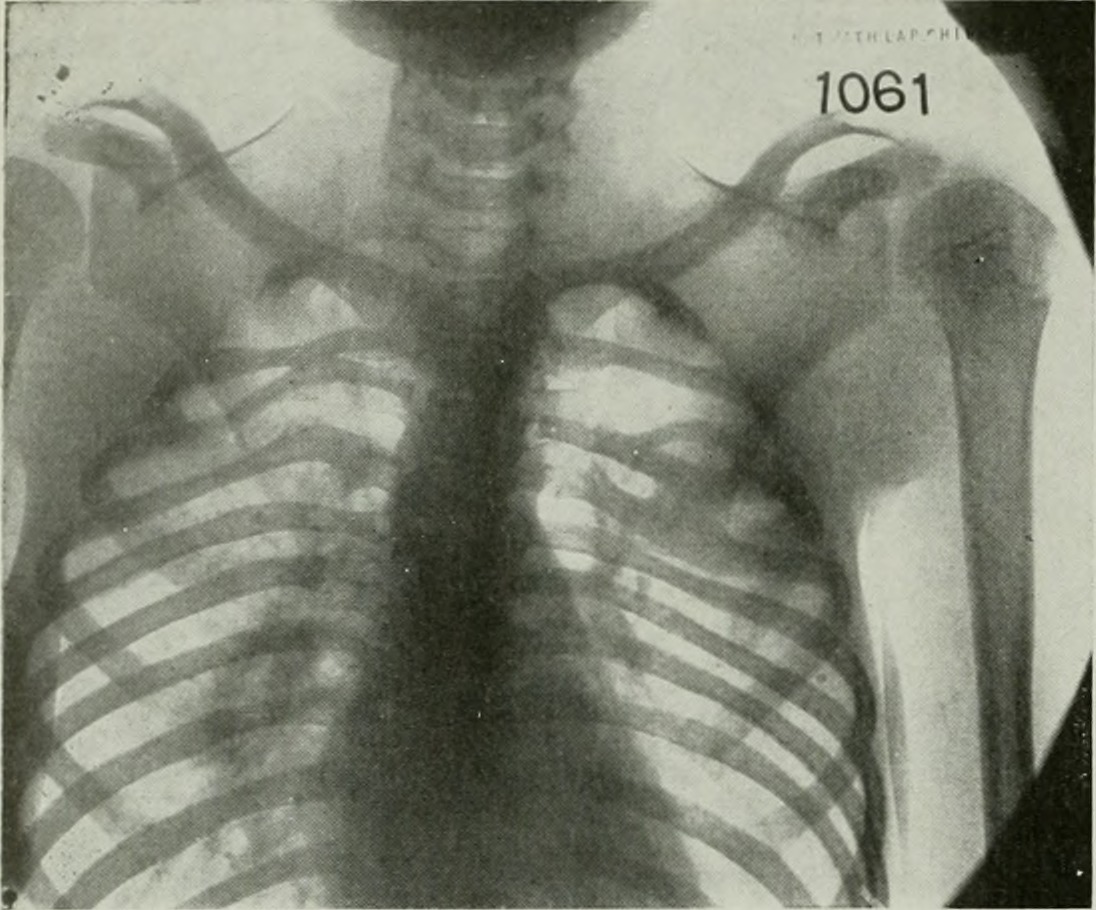

N eck pain is a personal experience that requires personalized assessment, treatment and diagnosis to get to root cause of the problem. In severe instances, where the neck pains a lot, one can be recommended to undergo neck fusion procedure. In cases where a patient experiences a chronic neck pain, a surgery or multidisciplinary diagnosis is needed. It is wise to understand that neck pain can occur to anybody at anytime. There are many reasons a person may have paining neck. Necks supports people’s head, where a head can be heavier as it can be more than 15 pounds. This weight be carried day in day out at times may pressure the neck to have stress on both the spine and the neck. People sitting while tilting their heads for a long time can experience pain in their necks. In addition, sleeping on the wrong way as well as bending, twisting and lifting things may cause strain on your body and lead to neck pain. However, if the pain becomes severe and uncontrollable, a neck fusion procedure can be the only solution to your health. Degenerative Disc illnesses which are common among senior people are another cause of pain on necks. Therefore, aging is a catalyst for pain on poor joint as person grows old he becomes prone to diseases such as spinal stenosis and osteoarthritis. Another common cause of paining neck is the trauma like whiplash that occurs when people are involved in an accident. Though the kind of pain experienced from aching neck is different for different individuals every person is susceptible of suffering from neck pain. Some victim will only experience pain in their necks when they tilt their heads, while others when they turn their heads to a certain direction. To some people, pain may last for hours while others experience pain for a certain period. If the pain in your neck persist, it is advisable to seek medical advice from professional and experienced physicians. Some of the most common treatment for neck pains is physical interventions and medications. One may take pain killers like muscle relaxants, anti-inflammatory or acetominiphine. On the other hand, a victim can decide to try massage therapy, physical exercise, acupuncture treatment, physiotherapy, heat treatment and other physical treatment recommended by your doctor. But in situation where the physical and simple medication fails to put away the pain in your neck, a surgery may be the only remedy. A neck pain victim may undergo discetomy. This is a medical method of extracting the whole or part of the infected disc on your neck. A surgeon too can prescribe fusion method. Neck fusion procedure aids completely discarding away pain by restoring spinal column firmness. [Photo: flickr.com]